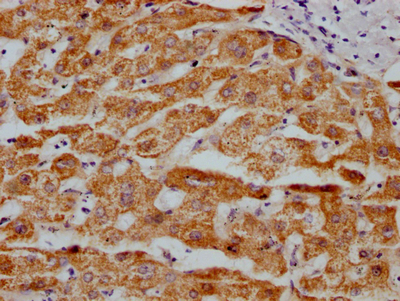

IHC image of CSB-RA250615A0HU diluted at 1:100 and staining in paraffin-embedded human liver tissue performed on a Leica BondTM system. After dewaxing and hydration, antigen retrieval was mediated by high pressure in a citrate buffer (pH 6.0). Section was blocked with 10% normal goat serum 30min at RT. Then primary antibody (1% BSA) was incubated at 4℃ overnight. The primary is detected by a Goat anti-rabbit IgG polymer labeled by HRP and visualized using 0.05% DAB.